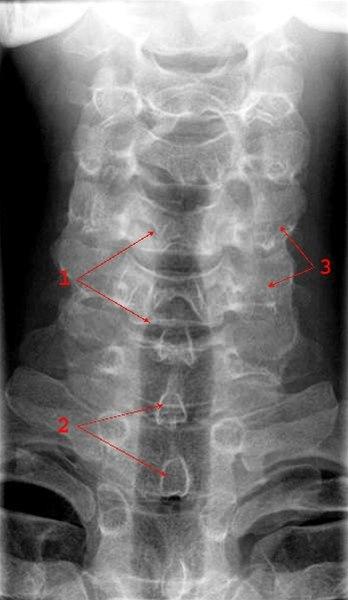

Normalt frontalbilde av cervikalcolumna (ryggsøylen, nakke)

- Trachea

- Processi spinosi (ryggtagger)

- Prosessus transversi (tverrtagger)